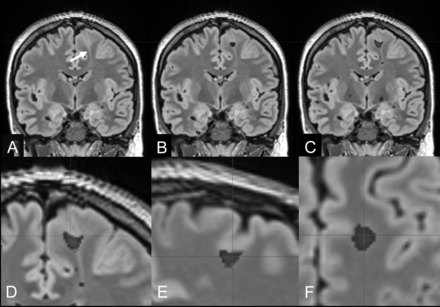

FCD IIb with a transmantle sign of the left superior frontal gyrus (bottom-of-sulcus dysplasia) in a 27-year-old man with right-sided sensory-motor seizures (patient 5). A, Reformatted 1-mm-thick coronal FLAIR section (arrow: transmantle sign of the FCD). B, Overlay of MPRAGE-based junction image abnormalities with z scores of >4. C, Overlay of MP2RAGE-based junction image abnormalities with z scores of >4. The MP2RAGE-based junction image matches the signal abnormalities at the gray matter junction as a characteristic feature of FCD type II (D–F, magnified coronal, sagittal, and axial views).

FCD with a transmantle sign of the right superior frontal gyrus (bottom-of-sulcus dysplasia) (FLAIR A and D) in an 11-year-old girl with left upper and lower limb somatosensoric aura and motor seizures (patient 20). The MPRAGE- (B and C) and MP2RAGE-based junction images (E and F) match the signal abnormalities at the gray matter junction as a characteristic feature of FCD type II. MP2RAGE delivers, in this case, higher contrast junction images and better lesion definition compared with MPRAGE.